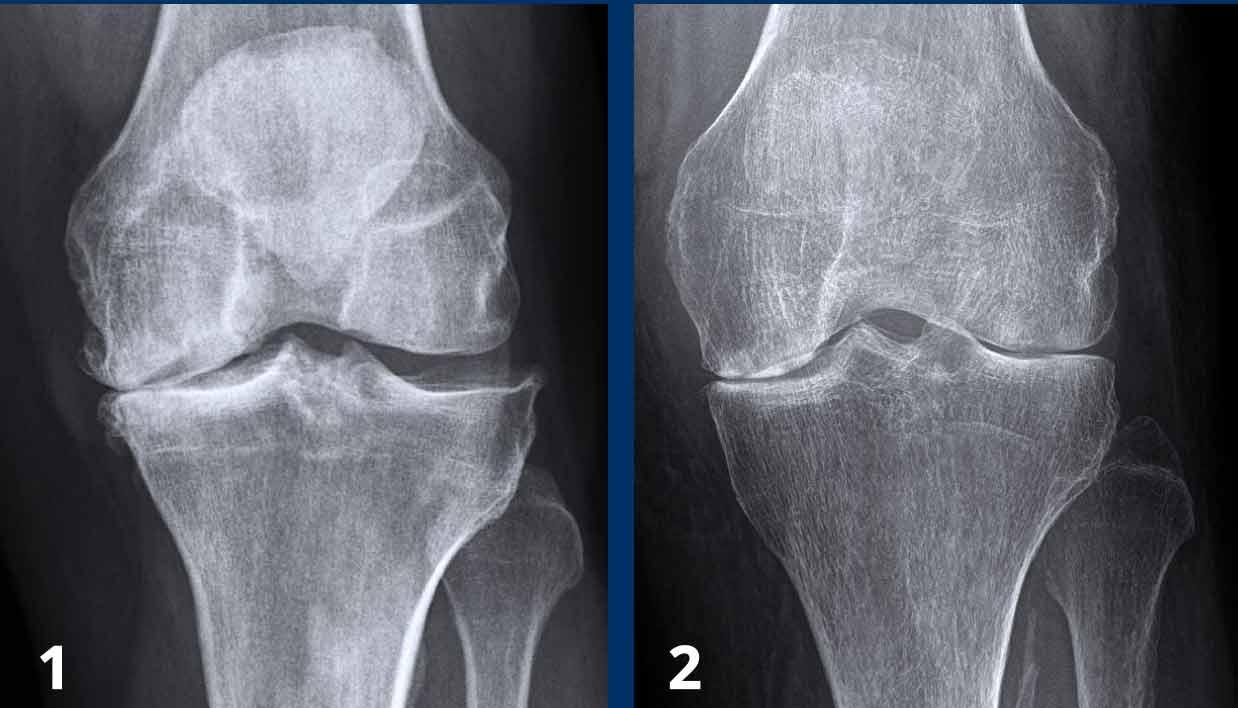

Tại khớp gối, thoái hóa khớp được phân loại theo thang điểm Kellgren và Lawrence.

Thang phân loại này có thể được áp dụng để đánh giá mức độ thoái hóa ở các khớp khác, tuy nhiên nó được thiết kế chủ yếu cho khớp gối.

Thoái hóa khớp gối

Hẹp khe khớp đùi-chày khoang trong mức độ vừa đến nặng, không đối xứng, kèm hình thành gai xương và xơ cứng xương dưới sụn (phân loại Kellgren-Lawrence độ 3-4).